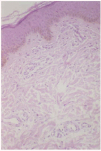

Una biopsia cutánea de la espalda mostró una hiperpigmentación melánica basal en la epidermis (fig. 3). La dermis superficial contenía algunos vasos ectásicos y melanófagos y en la dermis profunda se observaban células de aspecto fusiforme, que presentaban gránulos metacromáticos citoplasmáticos en la tinción de Giemsa (fig. 4).

Fig. 3.--Hiperpigmenatación de la membrana basal y vasos ectásicos en dermis (HE, x100).

Histológicamente, todas las formas de mastocitosis se caracterizan por un aumento de los mastocitos que pueden ponerse de manifiesto con tinciones especiales como Giemsa o azul de toluidina. Son frecuentes la hiperpigmentación de la capa basal y la presencia de eosinófilos.